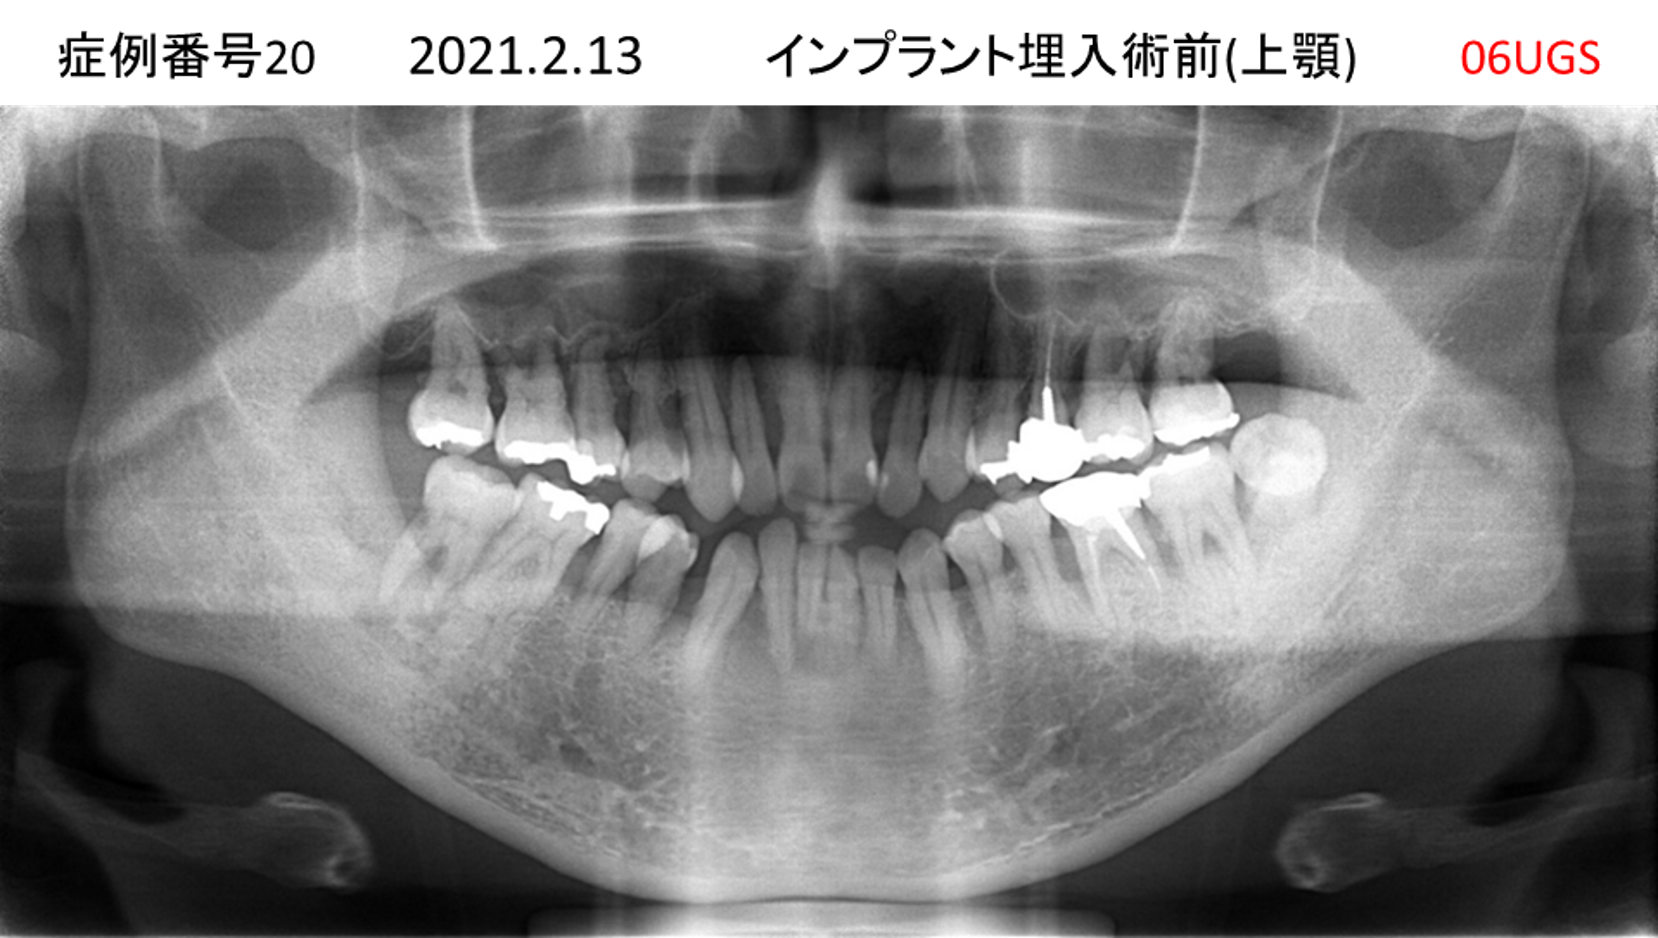

上の前歯が揺れてきてかめない患者様のインプラント症例

| 治療名称 |

インプラント |

| 治療費用 |

440万円+税 |

| 治療期間 |

6か月 |

| 患者さんの症状(主訴) |

上の前歯が揺れてきた。かめない |

| 治療内容 |

サイナスリフト、GBR、インプラント、即時荷重 |

| 治療結果 |

上の前歯の揺れが収まった。奥歯でしっかり噛める。 |

| 治療の注意点(リスク/副作用) |

インプラントが壊れたら再治療が必要 |